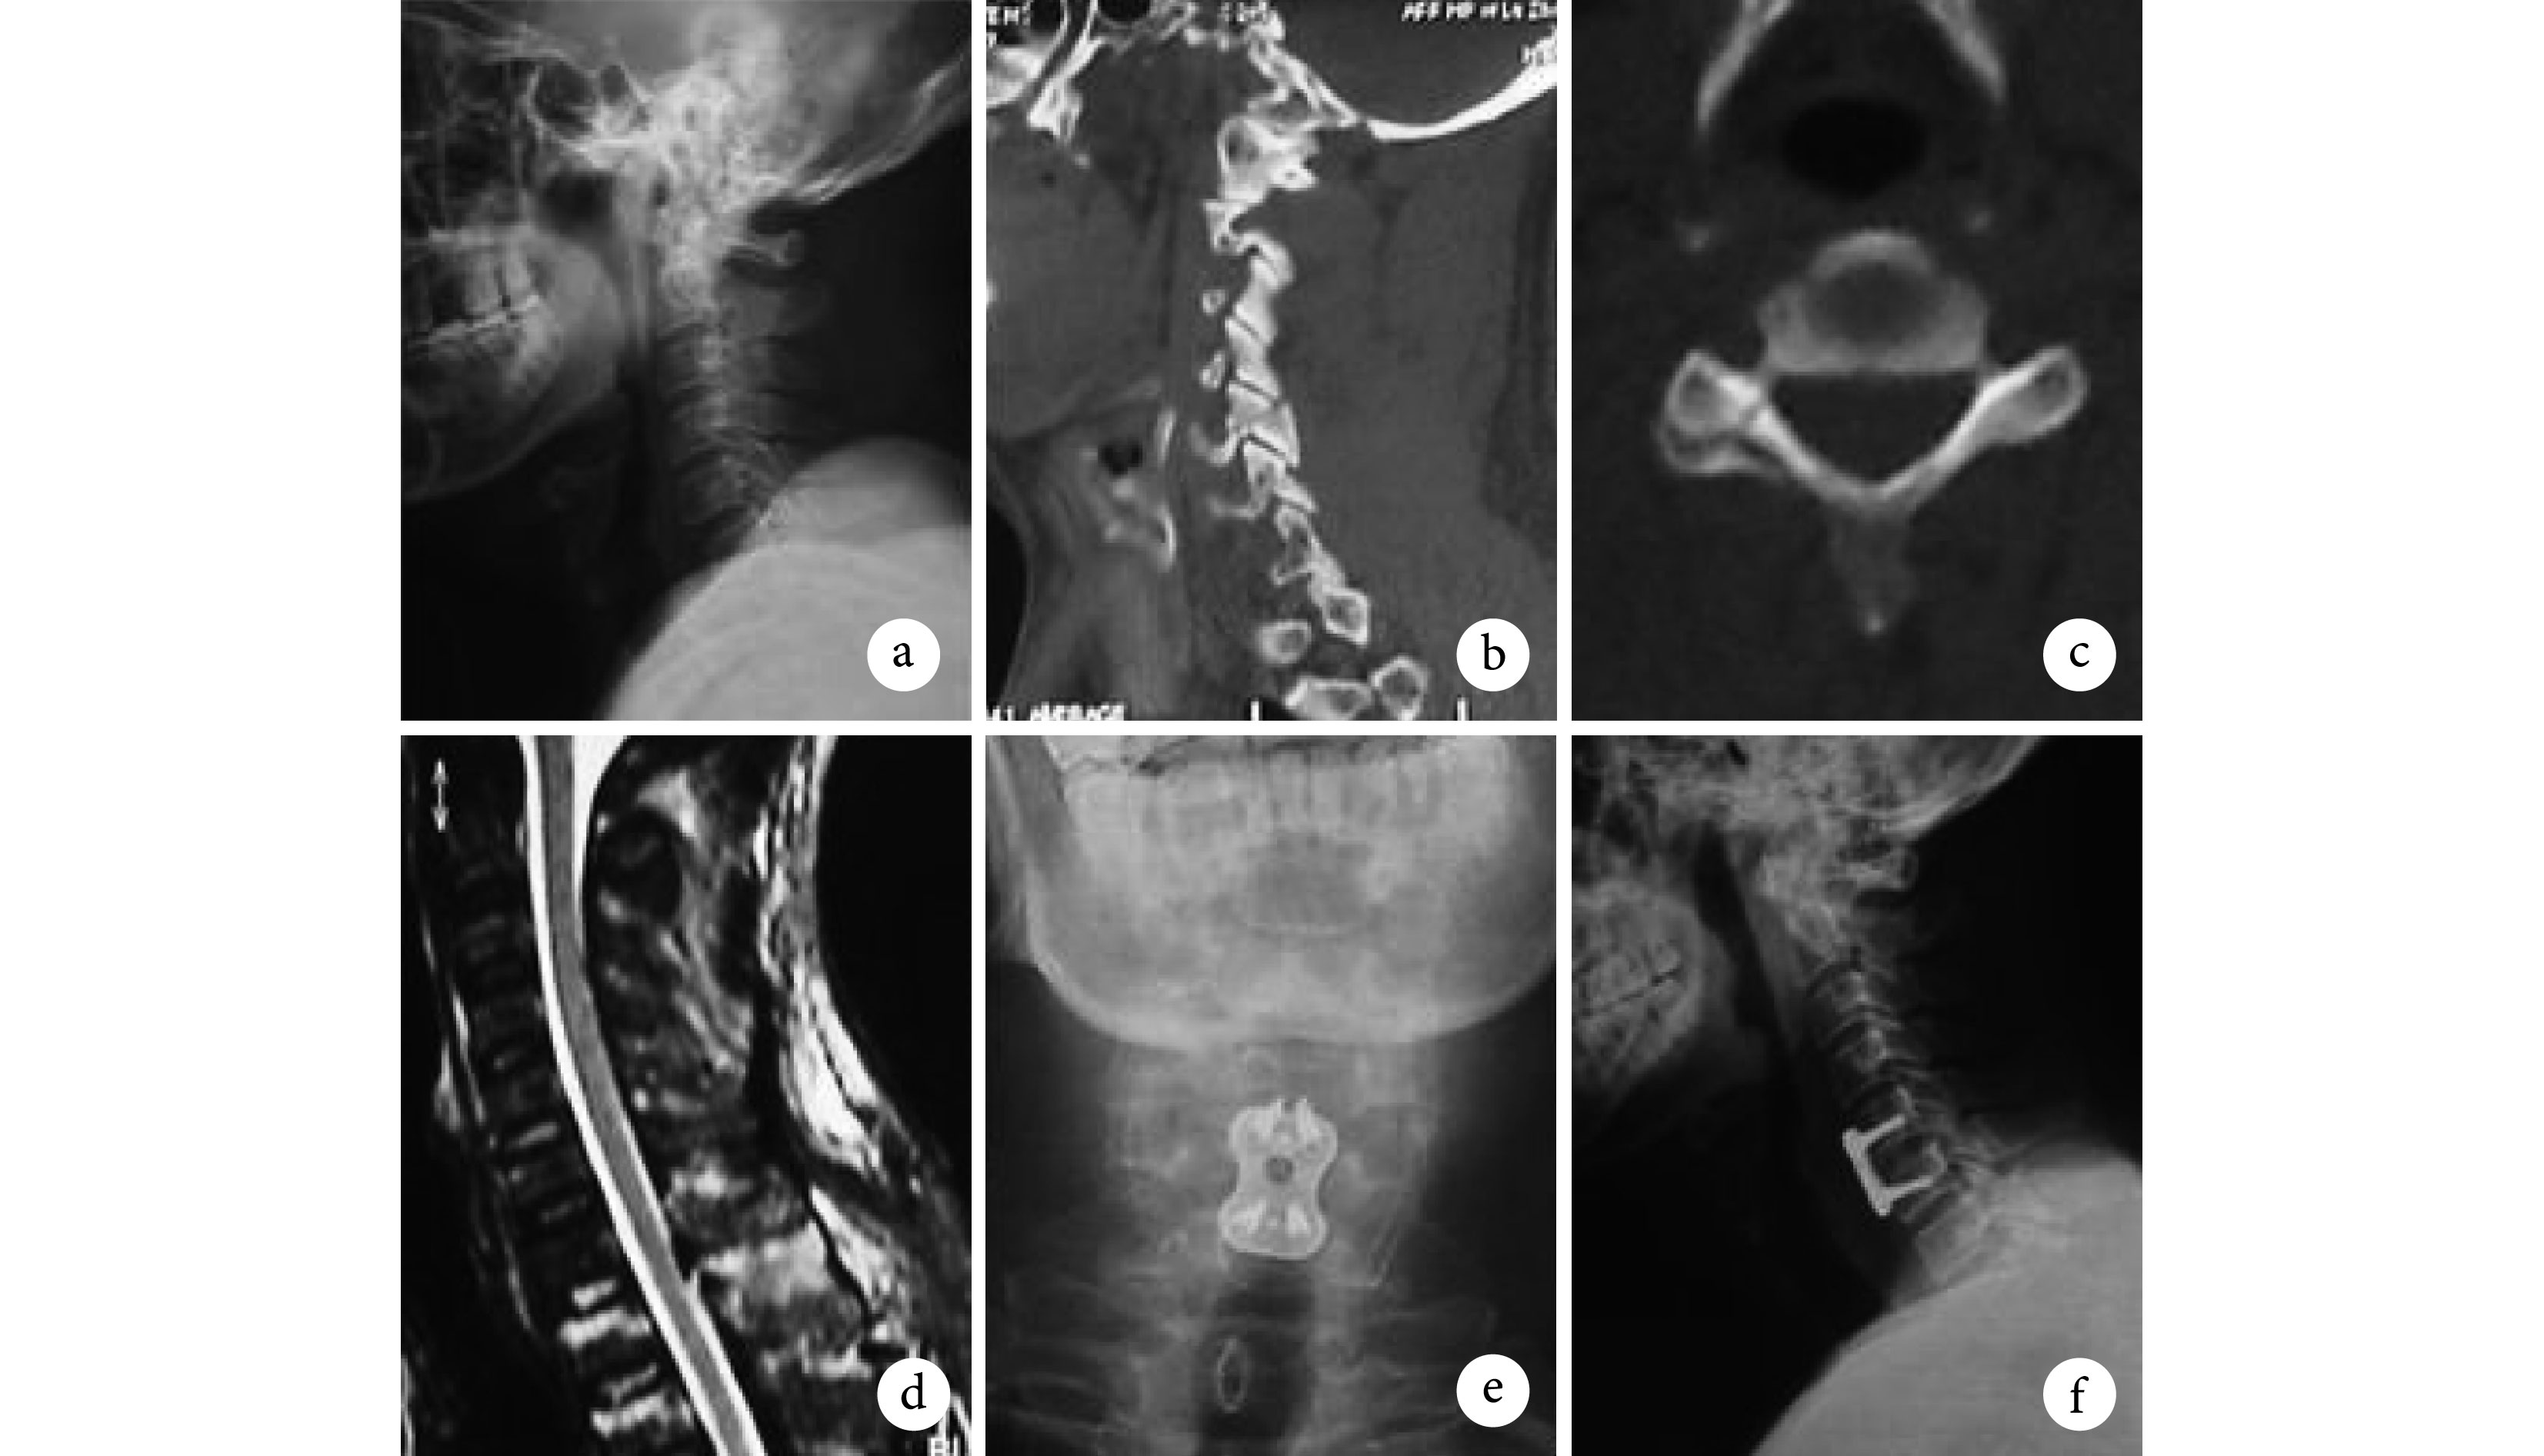

A1 型 35 例,采用頸托保守治療 2 例(1 例骨折愈合,1 例發生遲發性頸椎不穩接受前路 ACDF 手術),前路單節段 ACDF 手術 31 例,ACCF 手術 2 例(2 例患者合并頸椎管狹窄,脊髓損傷,為取得廣泛減壓采取 ACCF)(圖 1);A2 型 7 例,采用后路椎間孔減壓、椎弓根螺釘固定融合 4 例,前路單節段 ACDF+后路椎間孔減壓 2 例,前路單節段 ACDF+后路椎間孔減壓+側塊螺釘固定 1 例(圖 2); B 型 5 例,采用前路單節段 ACDF 手術(圖 3);C 型 21 例,采用前路雙節段 ACDF 手術 14 例,ACCF 手術 6 例,后路椎弓根螺釘固定+單開門椎管擴大成形術 1 例(圖 4)。術后出現 C5 神經根麻痹 1 例,頸椎前方切口血腫 2 例,肺部感染 3 例,無切口感染及神經損害加重病例。62 例(91.2%)患者獲得隨訪,隨訪時間 6~36 個月,平均 14 個月,全部患者獲骨性融合,無內固定失敗、后凸畸形、相鄰節段脫位等。脊髓損傷恢復至 D 級3 例,E 級 6 例;神經根損傷完全恢復 12 例,部分恢復 9 例。

患者男,47 歲,B 型骨折,Frankel E 級。a. 術前 X 線片顯示 C5 椎體向前移位;b、c. 術前 CT 示 C5 右側關節突間部骨折;d. 術前 MRI 顯示脊髓信號正常,C5-6 平面后方韌帶復合體高信號;e、f. 行 C5-6 椎間盤切除植骨鋼板內固定術后正側位 X 線片,顯示頸椎序列良好

患者男,42 歲,C 型骨折,Frankel E 級。a. 術前 X 線片顯示頸椎序列正常;b、c. 術前矢狀位 CT 示 C5 右側關節突間部骨折,橫斷位 CT 示骨折線波及右側椎板和右側椎弓根;d. 術前 MRI 顯示脊髓信號正常,C6-7 前縱韌帶不連續;e、f. 行 C5-6、C6-7 椎間盤切除植骨鋼板內固定術后正側位 X 線片顯示,頸椎序列良好